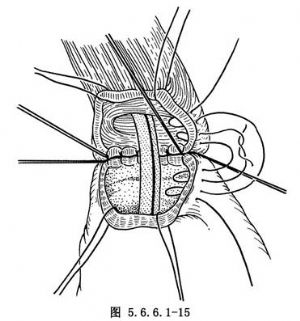

(4)常规食管胃端侧吻合:①先在预计切断食管的平面上方1cm处由食管边缘两侧分别用丝线穿过肌层与黏膜下层,与胃底部预计切开处的浆肌层缝合,两针之间的距离为食管的宽度(图5.6.6.1-10),图中食管壁上的虚线为准备切断食管的平面;②在两根缝线之间加缝数针,将食管后壁与胃底部浆肌层完全缝合(图5.6.6.1-11),图中胃壁上虚线为准备切开胃壁的部位;③切开胃壁浆肌层,但勿切透黏膜,将循行于黏膜下的每根血管用细丝线缝扎两处,然后在缝扎线之间切开胃黏膜。黏膜上切口开始不宜太大,在吻合过程中如嫌不足可再次切开(图5.6.6.1-12)。在切开胃壁之前应先用干纱垫置于吻合口后方以吸取切开胃黏膜后逸出的胃液,切开胃黏膜后迅速将吸引器头送入胃中吸净胃液;④沿预计切断食管的平面环绕食管切开肌层但勿切开黏膜,在食管肌层断面远侧约0.8cm的平面剪断食管黏膜,因留有足够的黏膜,吻合时十分便利,否则如在同一平面切断食管肌层及黏膜,由于后者的回缩使吻合操作相当困难;⑤将吻合口后壁食管全层的左右侧两角分别与胃壁切口的上缘全层用细丝线间断缝合,注意食管黏膜与胃黏膜必须对齐,缝线之间的间隔约为0.4cm,缝线结扎不能太紧以免术后局部组织水肿造成切割,成为发生吻合口瘘的主要因素(图5.6.6.1-13)。结扎线结打在腔内(图5.6.6.1-14);⑥将胃管经吻合口送入胃中,如果应用十二指肠饲食管,可在此时将引导饲食管的糖球一并送入胃中(图5.6.6.1-15),开始吻合前壁。由后壁转往前壁时,两侧转角处的缝线必须缝好,因在转角处容易发生瘘。吻合的最后4~5针最好先挂上线而不结扎,待全部缝合完毕时一次打结;⑦前壁第一层吻合完成以后,撤除原来置于吻合口后方的干纱布块,参加手术人员用无菌净水冲洗手套,将吻合使用过的器械前端用水洗净,用细丝线间断缝合吻合口前壁第二层,完成食管肌层及黏膜下层与胃底部浆肌层之间的缝合(图5.6.6.1-16);⑧将吻合口周围的胃壁用纱布向吻合口方向推送,结扎吻合口前壁第二层的缝线,使吻合口最后被套入胃壁中(图5.6.6.1-17);⑨将胃内引导十二指肠饲食管的糖球挤过幽门,清点台上敷料(包括纱布及纱垫)无误后,用中号丝线间断缝合膈肌。在胃越过膈肌处缝合不宜过紧,防止术后出现梗阻。将胃轻轻上推然后将胃壁与周围膈肌缝合6~7针,防止腹腔内脏器循此途径进入胸腔。注意不要用丝线将胃壁固定在胸壁上,此种缝线可能造成胃壁穿孔。如术者想采取措施减少吻合口的张力,可在近胃底部的胃大弯侧寻找一个切断大网膜的残结,用缝线穿过固定在纵隔胸膜上,同样可以达到吻合口减张的目的而无胃壁穿孔之虞。由第8肋间腋后线置入闭式引流管,检查胸内有无出血点或异物存留。用肋骨合并器将切口上下方的肋骨合拢,肋间组织用中号丝线缝合,冲洗胸壁肌肉,逐层关胸。将闭式引流管连接于水封瓶上。